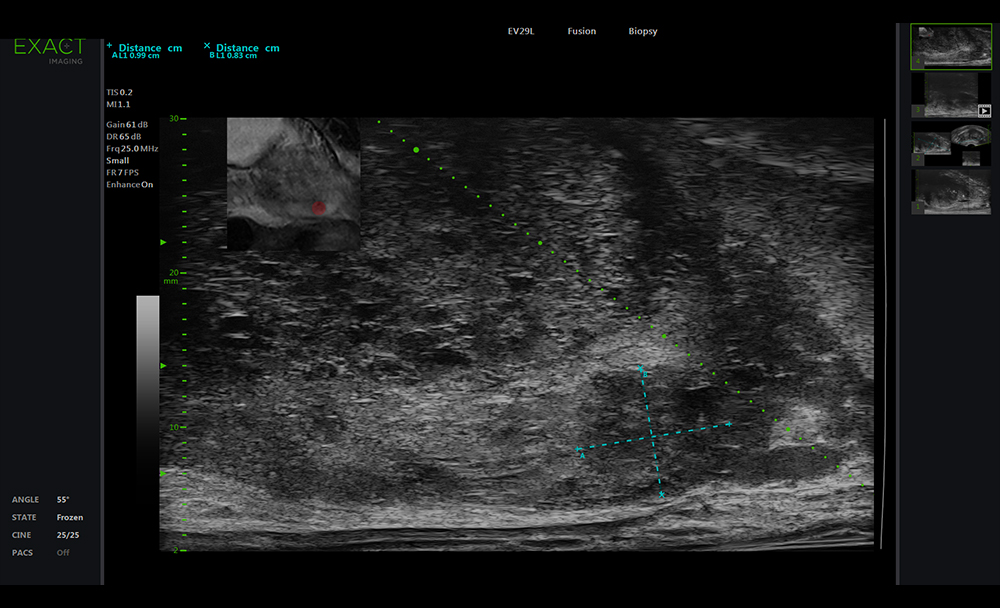

Mikroultraschall

Bei Verdacht auf das Vorliegen eines Prostatakarzinoms kann ein hochauflösender Ultraschall (Mikro-Ultraschall) erfolgen. Es muss nicht immer gleich eine Biopsie erfolgen.

MRT-Fusionsbiopsie

Bei Verdacht auf das Vorliegen eines Prostatakarzinoms kann eine Magnetresonanztomographie der Prostata durchgeführt werden. Ein verdächtiges Areal, sollte dann biopsiert werden.